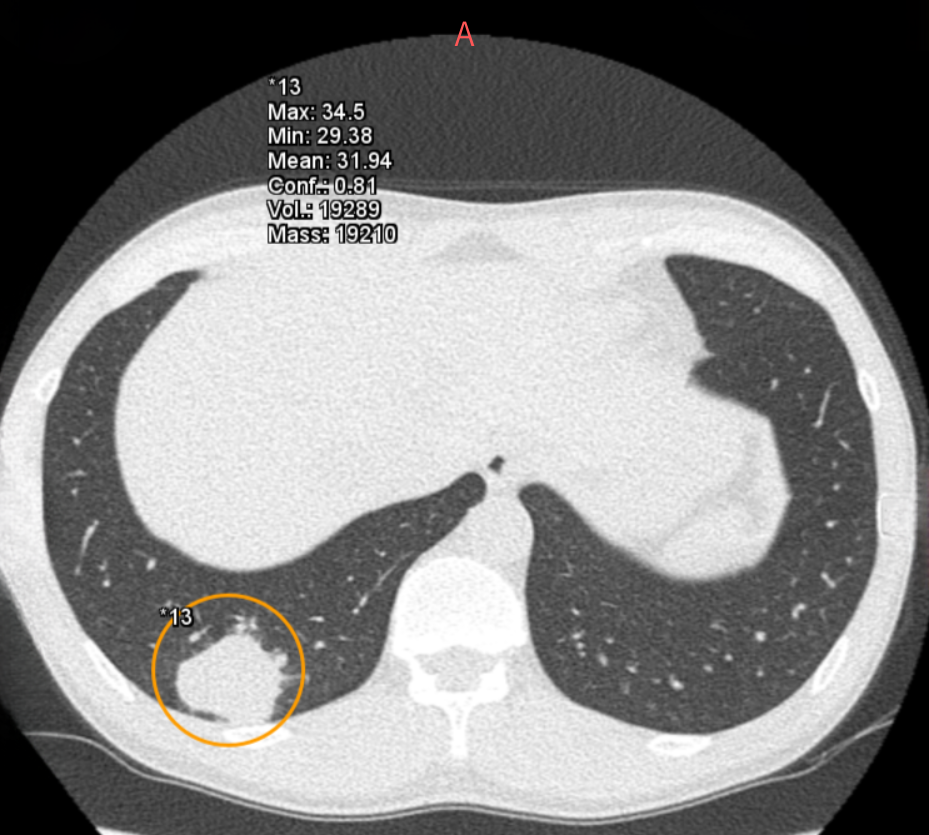

また、胸部X線AI「Plus.CXR」では著者が通常は指摘できない、径5mm前後の比較的小さな病変を指摘できます。

加えて、肺門部周囲の太い血管陰影とシルエットが明瞭に存在する淡い透過性の低下部を指摘することができました。これらは、十分な集中力で画像を参照していない場合見落とす可能性が高い所見だと思料されます(図1,2,3)。